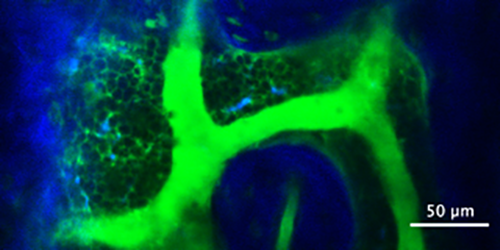

“Once in the bone marrow, the fluorescent dye happened to leak out of the blood vessels where it would then accumulate around the cells in the marrow, so what you end up getting is a bunch of dark circles with a bright background or negative contrast,” Spencer explained.

This negative contrast turned out to provide added benefits to live imaging, inadvertently revealing things like cell streaks in the blood flow and cells moving in the marrow. This in turn let Spencer measure things like blood velocity and blood vessel permeability, and also identify and track all the cells within the marrow space. Negative contrast isn’t a new concept, but Spencer, his graduate student Christian Burns and colleagues from Dr. Charles Lin’s lab at Harvard University are the first to use it in this way in the bone marrow and lymph nodes and publish the subsequent findings in a peer-reviewed journal.